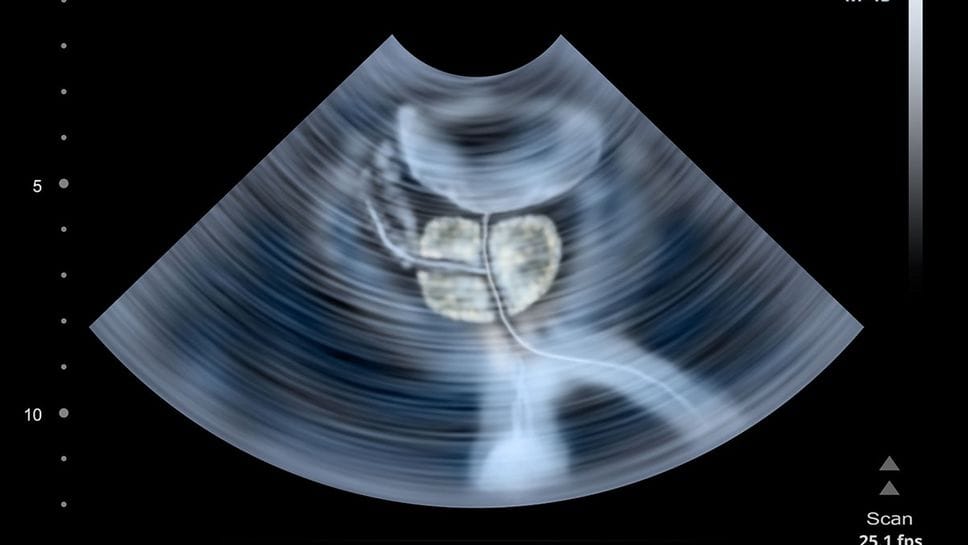

Prevenzione del tumore alla prostata: dal 17 al 22 novembre il Policlinico San Pietro, il Policlinico San Marco e il Centro diagnostico Treviglio aderiscono a Movember ,la campagna internazionale di prevenzione della salute maschile. È previsto il test gratuito del Psa che serve a misurare la quantità di un enzima prodotto dalle cellule della prostata, ritenuto un marcatore di potenziali problemi alla prostata.